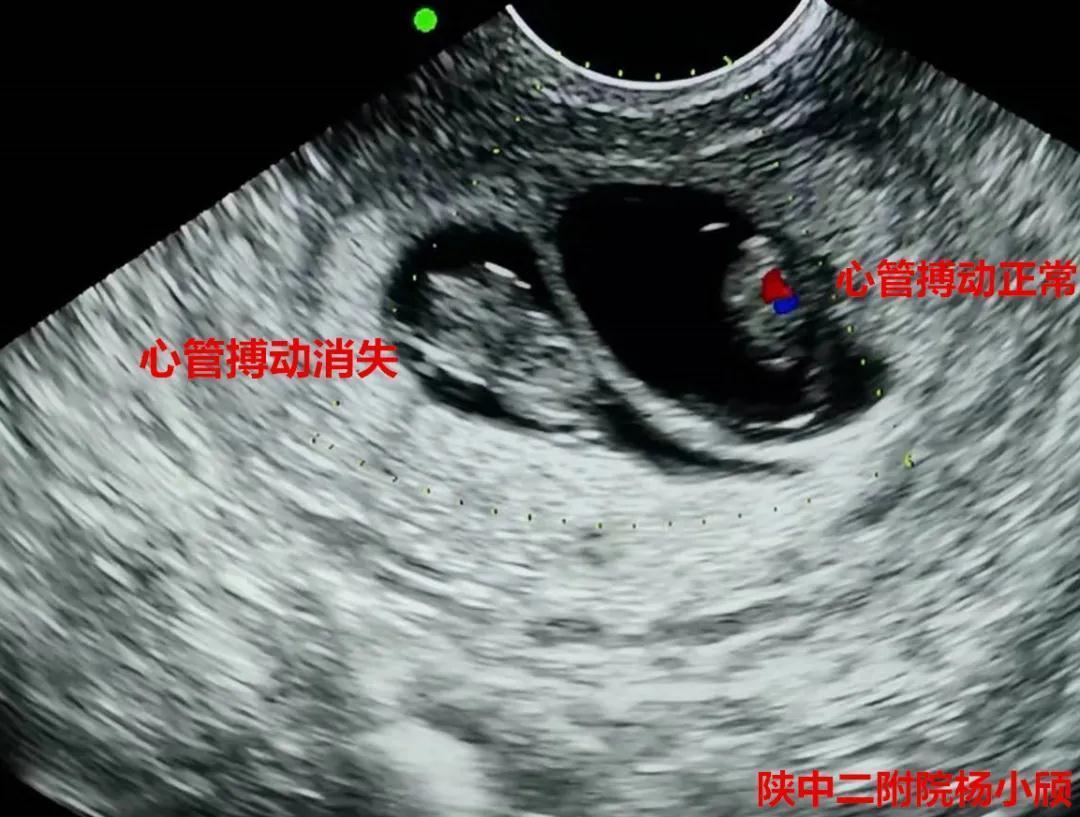

术后24小时阴超

在积极完善术前相关检查,排除手术禁忌症,充分告知患者及家属三胎妊娠的风险,签署知情同意书后,3月20日下午,杨小颀亲自操刀为患者实施了经阴道B超引导下选择性胚胎减灭术。手术顺利完成,病人病情平稳。术后24小时阴超提示,减胎孕囊胎心停止。7天后复查彩超提示,两胚胎存活,一胚胎停止发育。这标志着这台高难度的减胎手术圆满完成,达到预期效果,也再次彰显了陕西中医药大学第二附属医院(西咸新区中心医院)生殖内分泌科在减胎术方面的巨大进步。